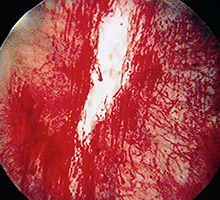

わが国では、ハンナ病変(正常の毛細血管構造を欠く特有の発赤粘膜)または膀胱水圧拡張後の点状出血の確認が重要視されています。

- 膀胱内にハンナ病変または膀胱拡張術後の点状出血を認める。